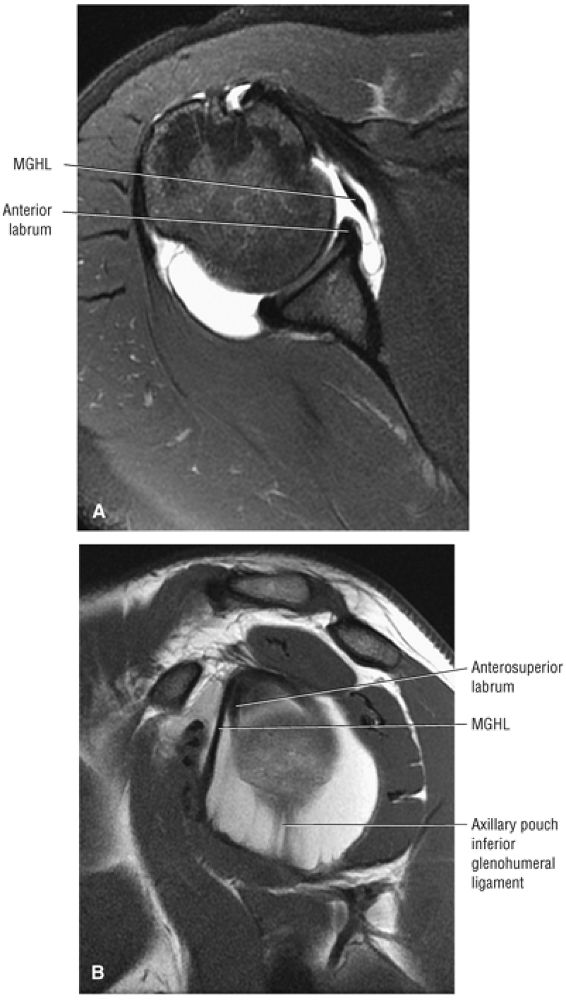

-

The MGHL is identified as a low-signal-intensity thin band or cord anterior to the anterior labrum, and the anterior band of the IGHL is between the anterior labrum and the subscapularis tendon. The MGHL may be closely applied to the anterior aspect of the anterior labrum or plastered against the subscapularis tendon, indistinguishable from the low-signal-intensity subscapularis without the benefit of intra-articular contrast. The SGHL is identified at the level of the coracoid and the biceps tendon.

The low-signal-intensity glenoid labrum is also defined on sagittal images that transect the glenohumeral joint. The anterior band of the IGHL can be seen extending anterior and superior to become the anterior labrum. The MGHL is seen anterior to the anterior labrum. The subscapularis tendon is located anterior to the MGHL. This relationship is constant, even though the MGHL may be variable in size and shape. The MGHL may also be absent. The axillary pouch extends between the anterior and posterior bands of the IGHL.